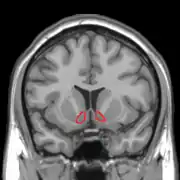

| Прилегающее ядро на МРТ головного мозга человека |

Сенсибилизация — концепция в психологии, объясняющая тот феномен, что люди после повторного приема вызывающего болезненное пристрастие вещества, независимо от вызываемого им чувства удовольствия и часто вопреки пониманию вреда, испытывают ещё большее пристрастие и тягу к повторному потреблению[1][2]. Концепция была предложена на основании опытов, в ходе которых экспериментальным животным вводили психостимуляторы, причём повторное введение лекарства вызывало усиленную психомоторную реакцию на введение прежней дозы[3][4]. Считается, что причина этого явления может быть связана со стойкими изменениями в прилежащем ядре, компоненте так называемого центра удовольствия.

Сенсибилизация — в разной степени выраженный у разных индивидов, специфический в отношении определенного вещества эффект, не связанный с перекрёстными реакциями, хотя она также может быть эффектом многих индуцирующих зависимость лекарств. Этот процесс является противоположностью формированию привыканию (габитуации). Сенсибилизация приводит к снижению чувствительности в области прилежащего ядра. Вследствие этого, ядро может активироваться уже минимальными дозами, а иногда и ассоциированными с наркотиком раздражителями. Так возникает «управляемая влечением» мотивация с импульсивным побуждением к действию. Эта мотивация манифестирует, прежде всего, в таких подкорковых центрах как полосатое тело. Эта так называемая «возбуждающая сенсибилизация» может объяснить феномен, заключающийся в том, что зависимый от какого-либо вещества больной, независимо от субъективного чувства удовольствия, испытывает чувство, вынуждающее снова найти и принять соответствующее наркотическое вещество. При этом данный процесс и следующие за ним действия и поступки в их целенаправленности не воспринимаются больным как насильственные, так как в этом случае не обязательно дело доходит до осознанной непреодолимой потребности в соответствующей субстанции.

Нейробиологический коррелят процессов сенсибилизации не вполне ясен. Возможно, этот процесс вносит решающий вклад в так называемою «наркотическую память», причем в её реализации, как полагают, участвует взаимодействие многих структур (в том числе, гиппокампа). В этой связи можно думать о вовлечении в процесс стойких изменений дофаминергической нервной передачи в прилежащем ядре, например, о повышении активности дофамина или сенсибилизации D1-дофаминовых рецепторов. Считается, что играть решающую роль при этом может развитие долгосрочного потенцирования в вентральном отделе полосатого тела и обусловленное им изменение глутаминергической нервной передачи[3].